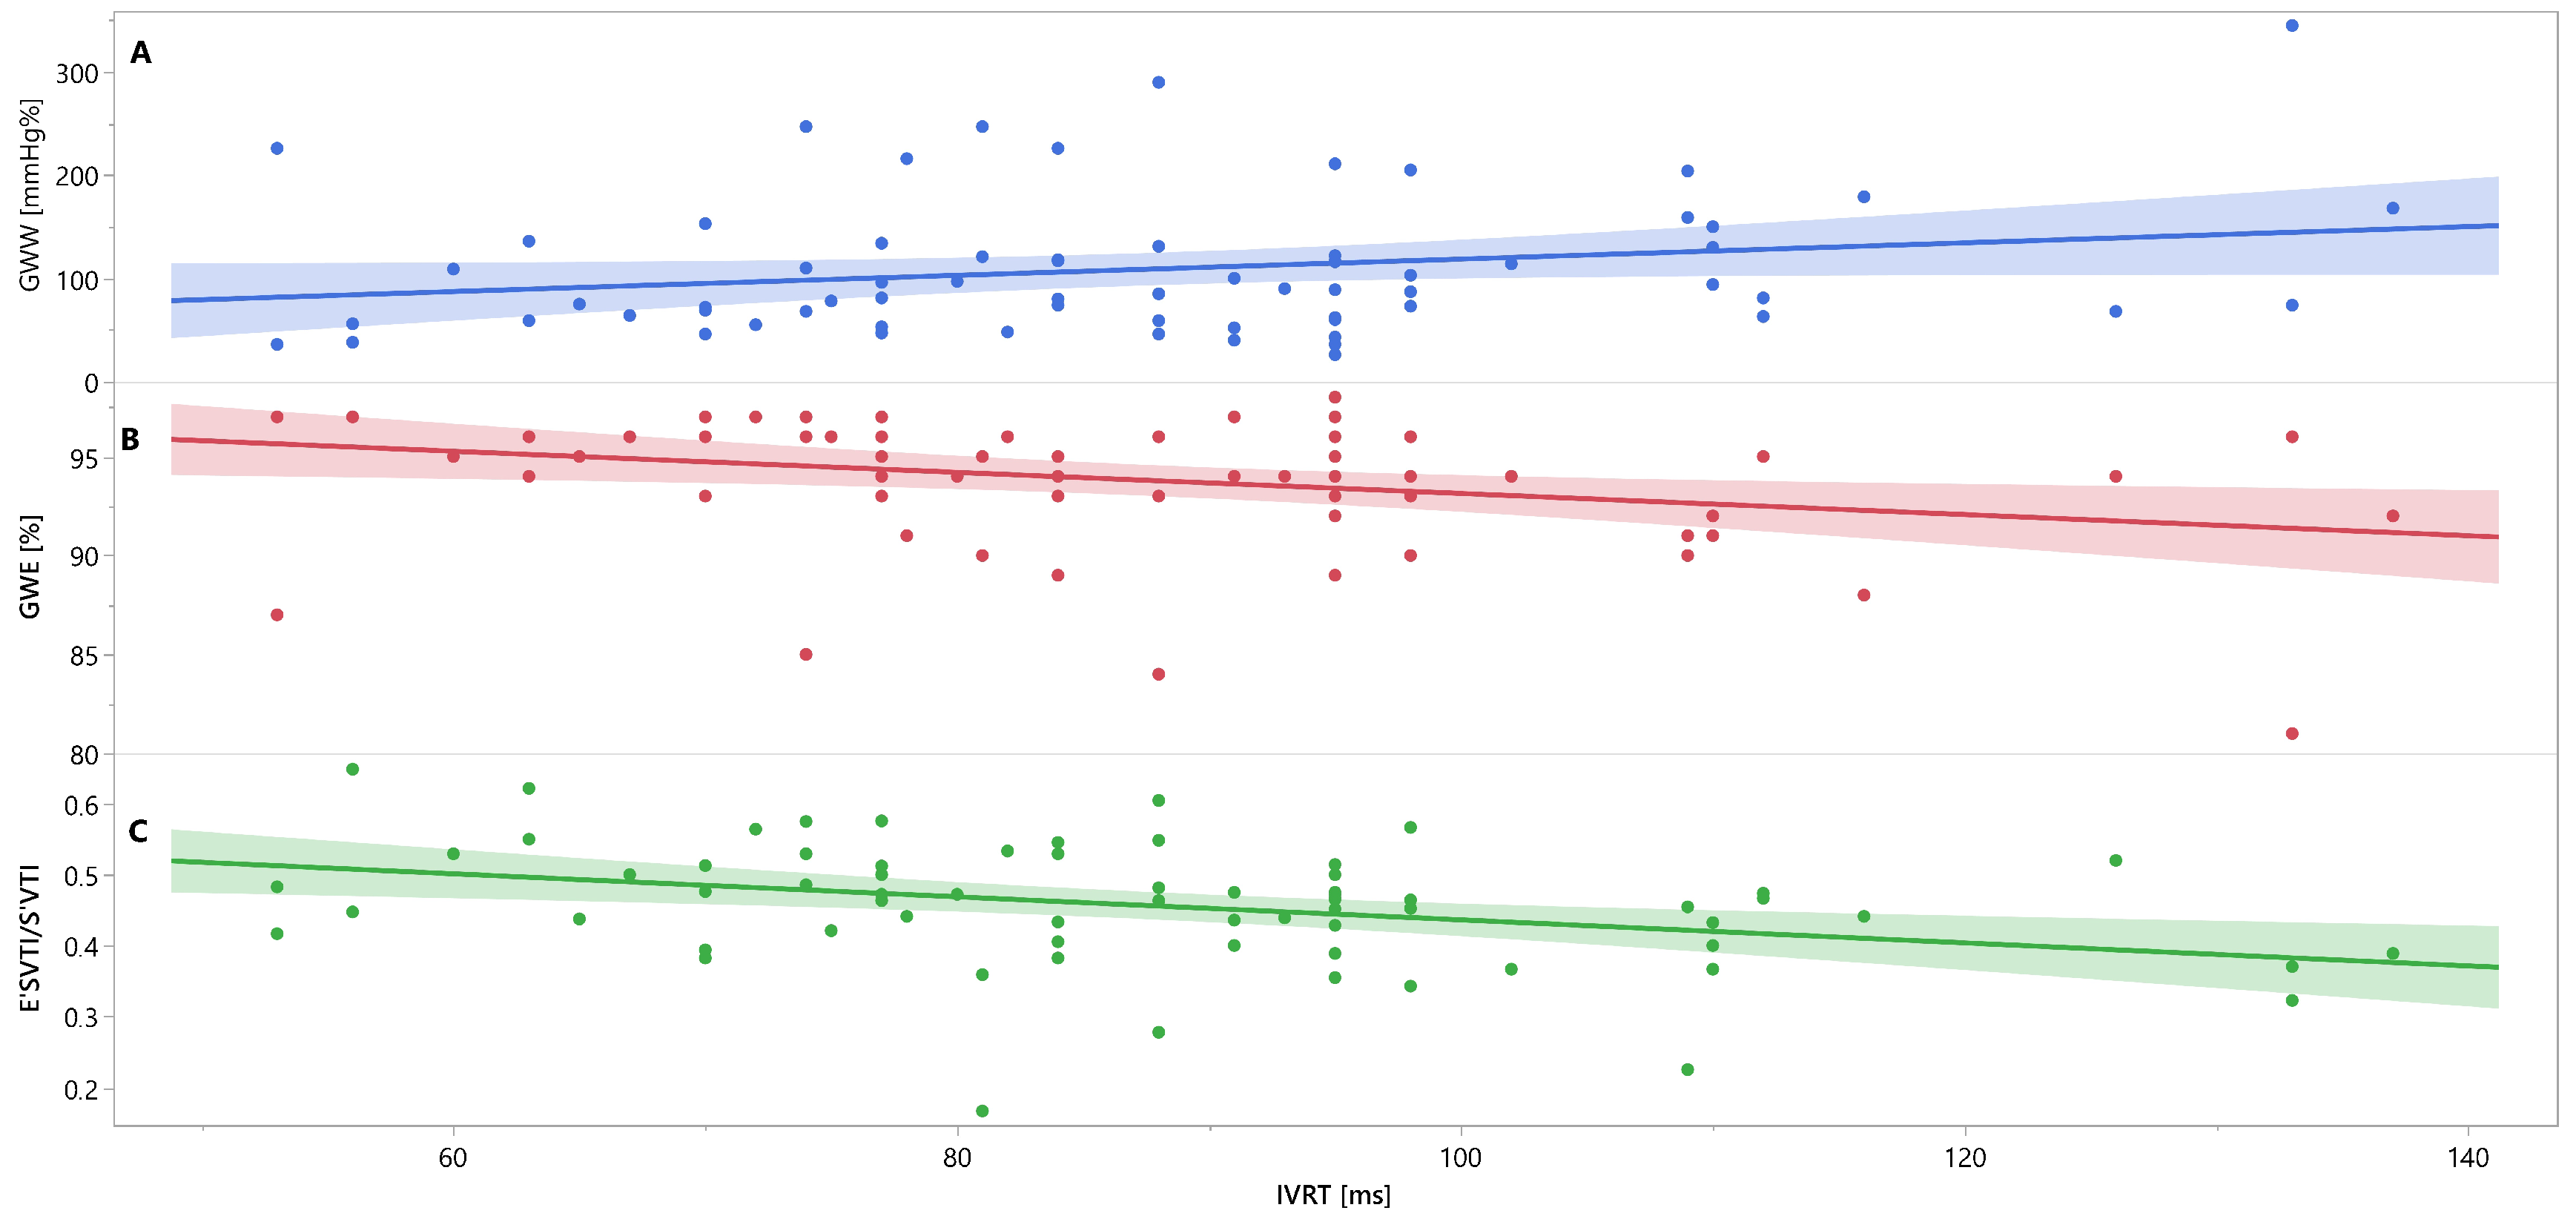

Mutual associations between PSD, GWW, GWE, IVRT and E′VTI/S′VTI are additionally shown in Figure 3, Figure 4 and Figure 5 as linear regressions.

Figure 4.

Linear regression lines for associations between IVRT and GWW (panel A, line and points in blue), GWE (panel B, line and points in red), and E′VTI/S′VTI (panel C, line and points in green) in healthy people. Abbreviations: E′VTI/S′VTI—systolic–diastolic coupling, GWW—global wasted work, GWE—global work efficiency, IVRT—isovolumetric relaxation time.